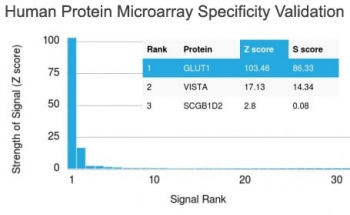

GLUT1 Antibody / SLC2A1

| Description | Recognizes a protein of 55kDa, which is identified as GLUT-1. Glucose transporters are integral membrane glycoproteins involved in transporting glucose into most cells. There are many types of glucose transport carrier proteins, designated as Glut-1 to Glut-12. Glut-1 is a major glucose transporter in the mammalian blood-brain barrier. It is expressed in high density on the membranes of human erythrocytes and the brain capillaries that comprise the blood-brain barrier. Glut-1 is expressed at variable levels in many human tissues. Overexpression of Glut-1 has been linked to tumor progression or poor survival of patients with carcinomas of the colon, breast, cervical, lung, bladder and mesothelioma. Glut-1 is a sensitive and specific marker for the differentiation of malignant mesothelioma (positive) from reactive mesothelium (negative). |